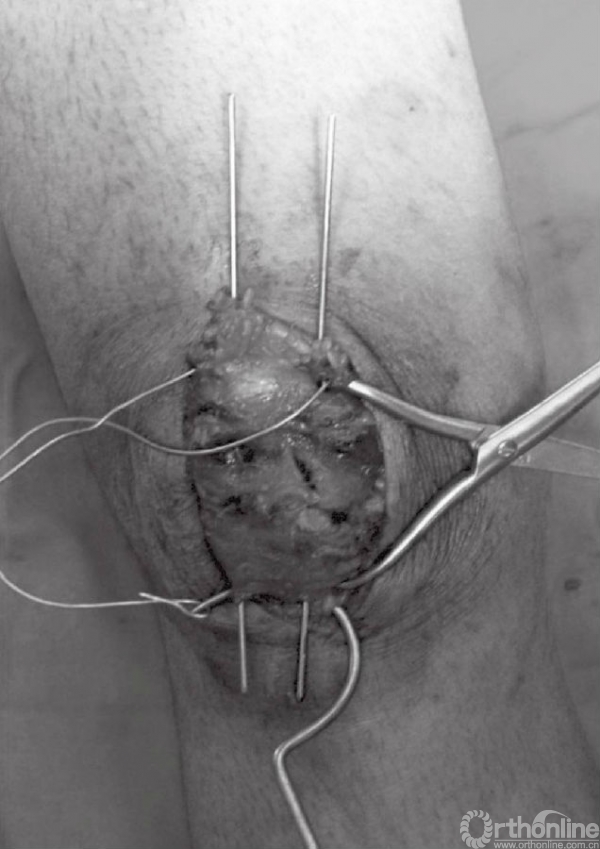

钢缆以“8”字形的方式穿行于髌骨上方。钢缆的一端应留长并做一圆圈,另一端在近髌骨下极处穿过髌韧带(图12)。用捆绑器将钢缆两端系紧。同时收紧髌骨两极的钢丝圈,这可以用钢丝钳或者简单的钳夹完成。钢丝收紧时注意先拉后收紧,这可以防止钢丝重叠,并提供良好的张力。同时收紧可提供两点张力和统一的收紧效果(图13和图14)。钢丝拉紧直至关节边缘微微开启。在膝关节屈曲时该间隙闭合,并在骨折面提供均匀的压力。张力带不应过分紧张,张力过大可导致骨折移位。此时,屈曲膝关节,观察内固定的稳定性以及骨折端的情况。

图12 钢缆末端做“8”字形,在近髌骨下极处穿过髌韧带

图13 钢缆末端以张力带固定装置固定。同时,张力带另一端用止血钳旋紧

图14 最后用线钳做最后的张力带旋紧固定,注意先拉后旋紧